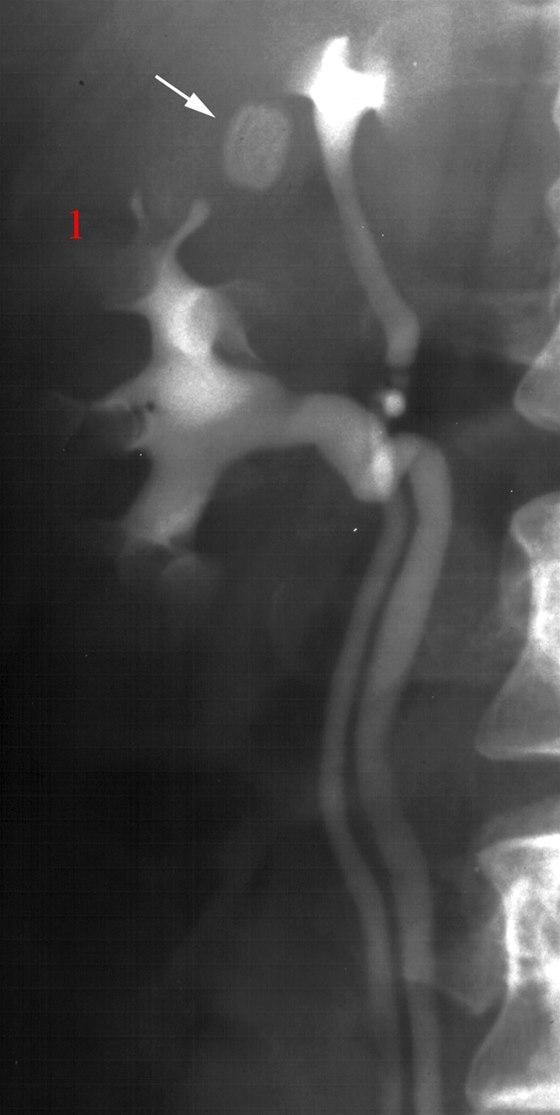

Dobbelt nyrebekken i høyre nyre (1)

Som bifunn sees en tablett i tarmen (pil)